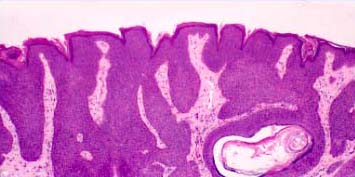

Atlas of skin histopathology

Seborrheic keratoses = التقران الدهني